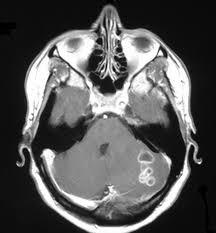

1. Agenesia

1. hipoplasia

1. Arnold Chiari

1. lesiones vasculares

1. Alteraciones metabolicas

1. Atrofias cerebelosas